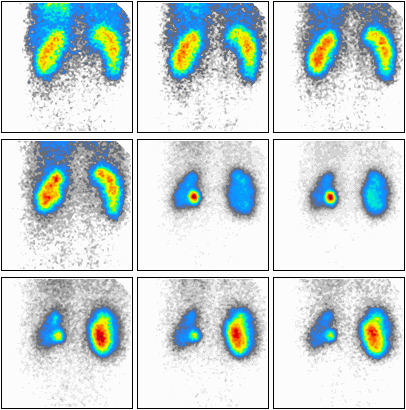

Podczas którego badania zostały zarejestrowane przedstawione obrazy?

A. Scyntygrafii nerek.

B. Scyntygrafii tarczycy.

C. Tomografii nerek.

D. Ultrasonografii tarczycy.

Na zarejestrowanych obrazach badania renoscyntygraficznego widać, że prawa nerka pacjenta

A. wykazuje opóźnione gromadzenie radioznacznika.

B. wykazuje opóźnione wydalanie radioznacznika.

C. nie gromadzi radioznacznika.

D. gromadzi prawidłowo radioznacznik.